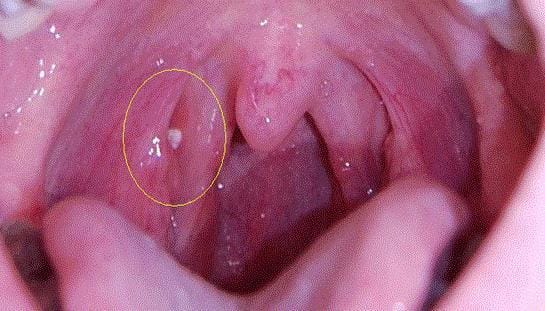

Bademcik taşları, bademciklerin yüzeyinde küçük çakıl taşları belirdiğinde ortaya çıkar. Taşlar beyaz veya sarı görünebilir. Bademcik dokusunun derinliklerinde oluşurlarsa, taşlar görünmeyebilir.

Bademcik kızarıklığı ve tahrişi, bademcik taşlarının yaygın belirtileridir. Bazı durumlarda, bademcik taşları kronik bademcik iltihabına veya bademcik iltihabı adı verilen bademcik enfeksiyonuna neden olabilir.

Büyük bademciklere sahip kişilerde bademcik taşı oluşma riski daha yüksektir. Büyük bademciklerin geniş bir yüzey alanı vardır ve bu alanlarda yiyecek parçacıklarının birikip bademcik taşlarına dönüşebileceği delikler oluşur.